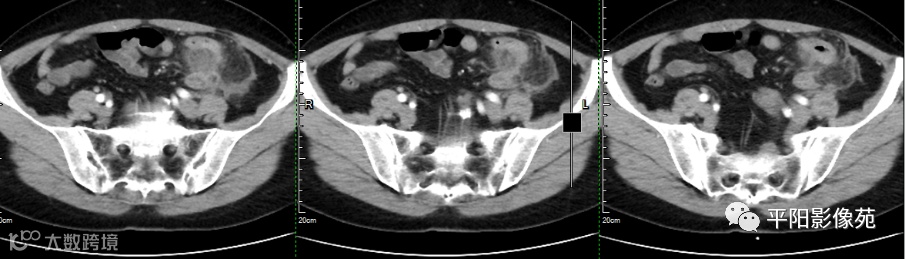

影像检查

全内脏翻转并左侧阑尾炎

完全内脏转位是指心脏、肺部、横膈及腹腔脏器等全部内脏呈180°转位,因此又被称为“镜面人”,其发生率0.5/10 000~2/10 000。